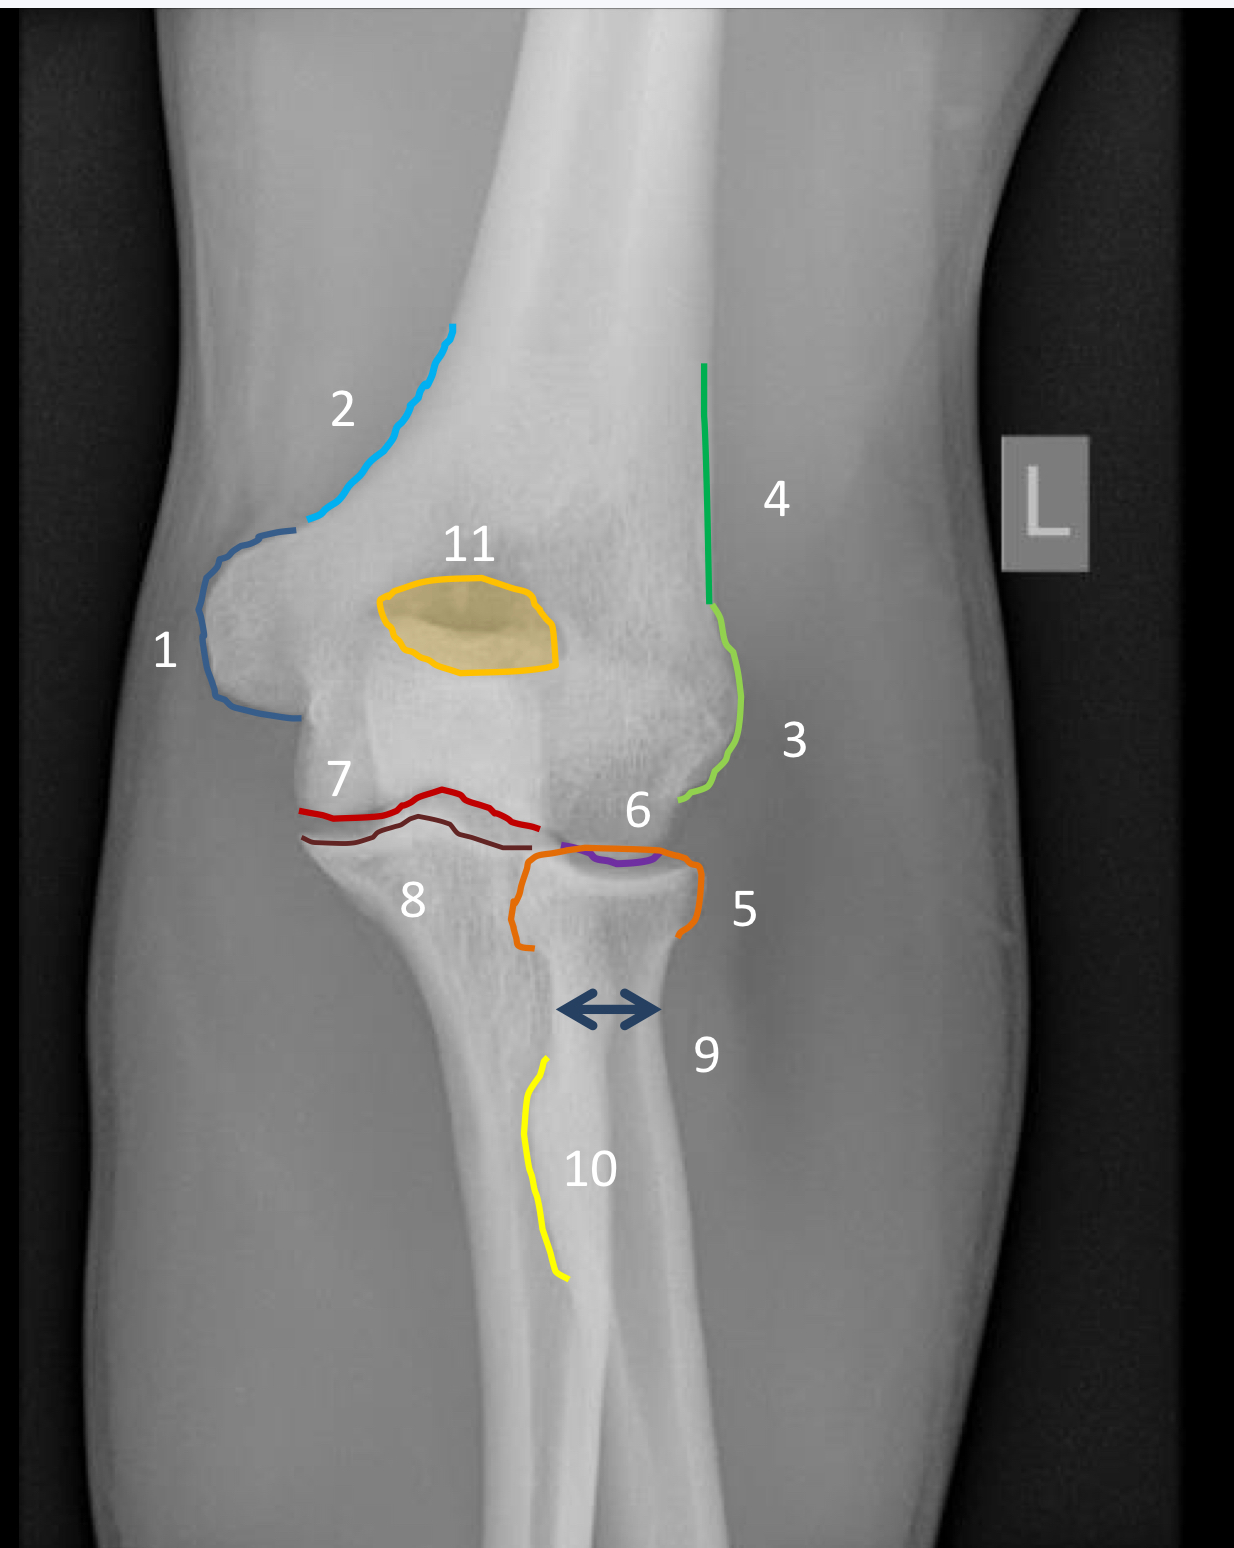

1?

medial epicondyle

2?

medial supracondylar ridge

3?

lateral epicondyle

4?

lateral supracondylar ridge

5?

radial head

6?

capitellum

7?

trochlea

8?

anterior trochlear notch including coronoid process

9?

neck of radius

10?

radial tuberosity

11?

olecranon foassa (and superimposed coronoid process)